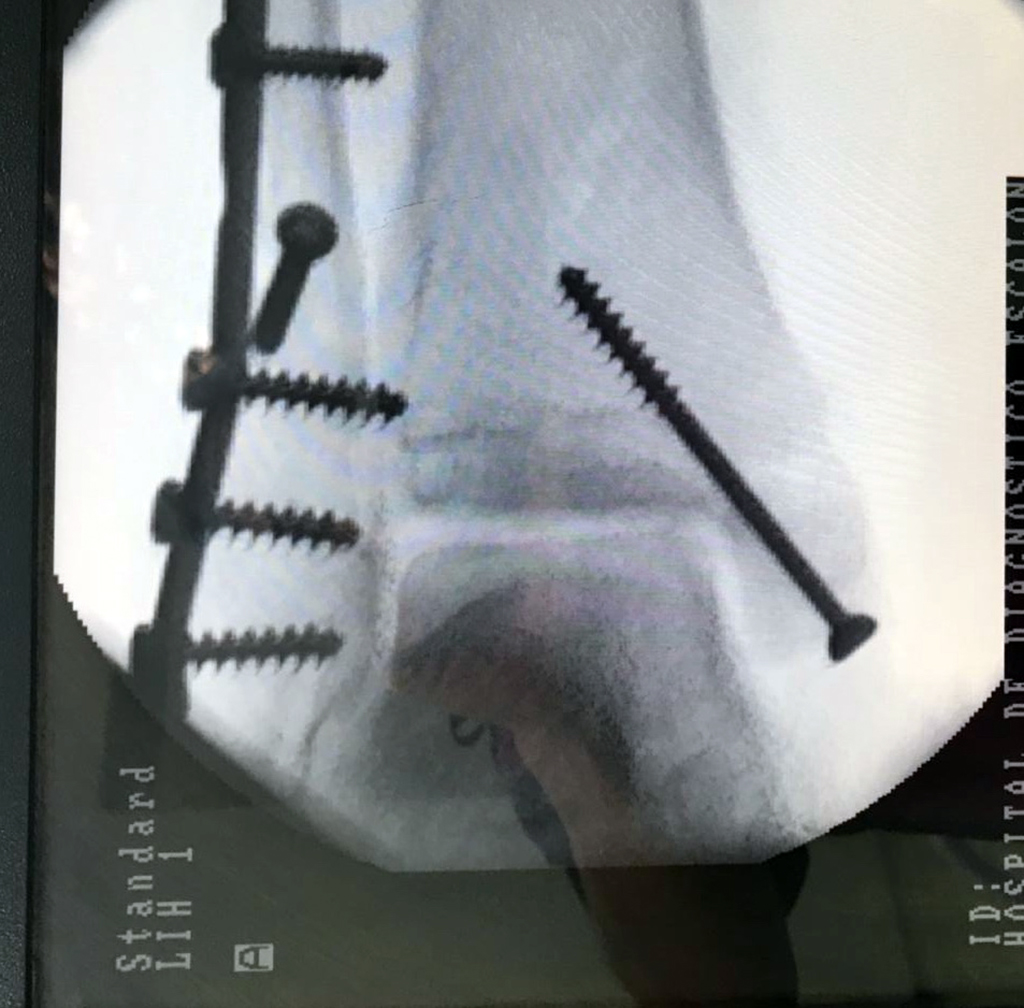

Cuando se necesita cirugía, es probable que esta implique el uso de clavijas de metal, tornillos o placas para sostener los huesos en su lugar mientras la fractura se consolida. Los elementos de soporte pueden ser temporales o permanentes.

Cirugía de Tobi...